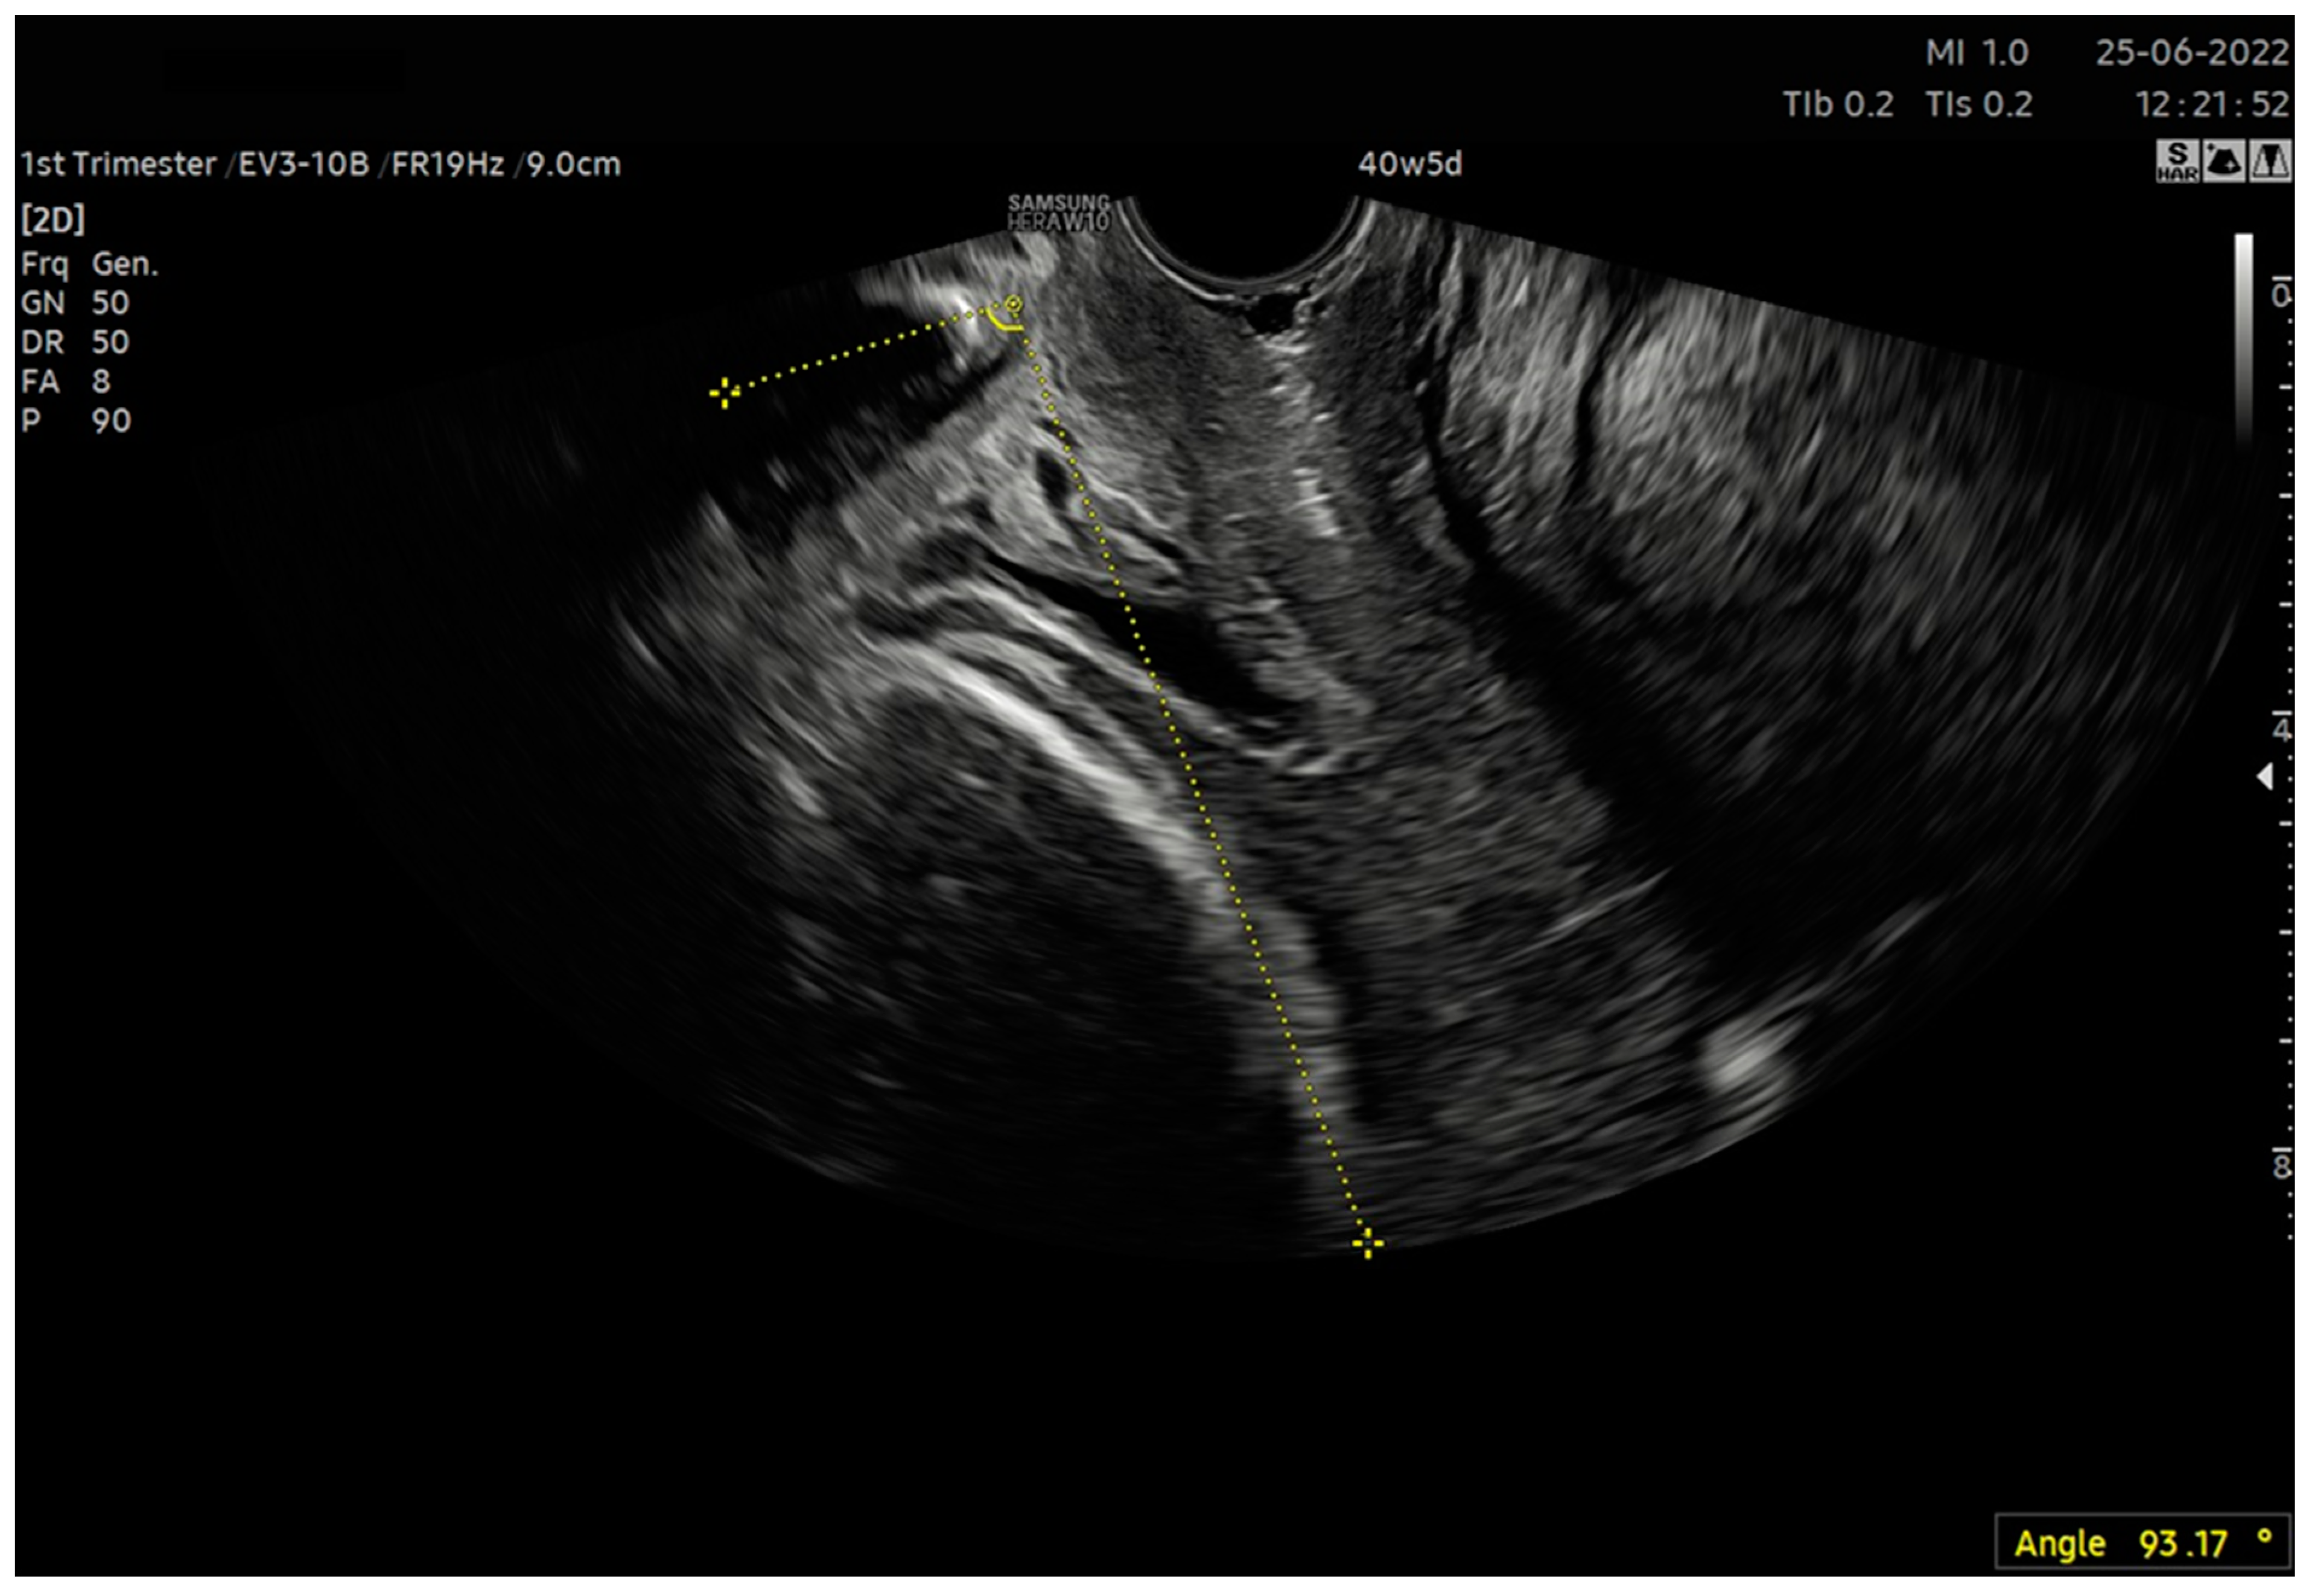

| 6. After calculating the E-Cervix parameters, volumetric image acquisition of the cervix was performed. The 3D image was rotated so that the external os of the cervix was presented en face on the screen; then, we measured the widest dimension of the external cervical os (dilatation—Figure 1). 7. We withdrew the transducer to the area of the vaginal os. 8. The transducer was placed in the vaginal axis; the vagino–cervical angle (VCA) measurement was performed after turning on the “central transducer line” option; the second line was guided tangentially to the axis of the cervical canal. In the case of a bent canal, the line was drawn tangentially to the end part contacting the vagina. We measured the angle formed at the intersection of the abovementioned lines (Figure 3). 9. We measured the AoP with the transducer located near the vaginal opening by drawing two lines—tangent to the long axis of the cross-section through the pubic symphysis and through the bone point of the fetal head being the most advanced in the birth canal (Figure 2). |